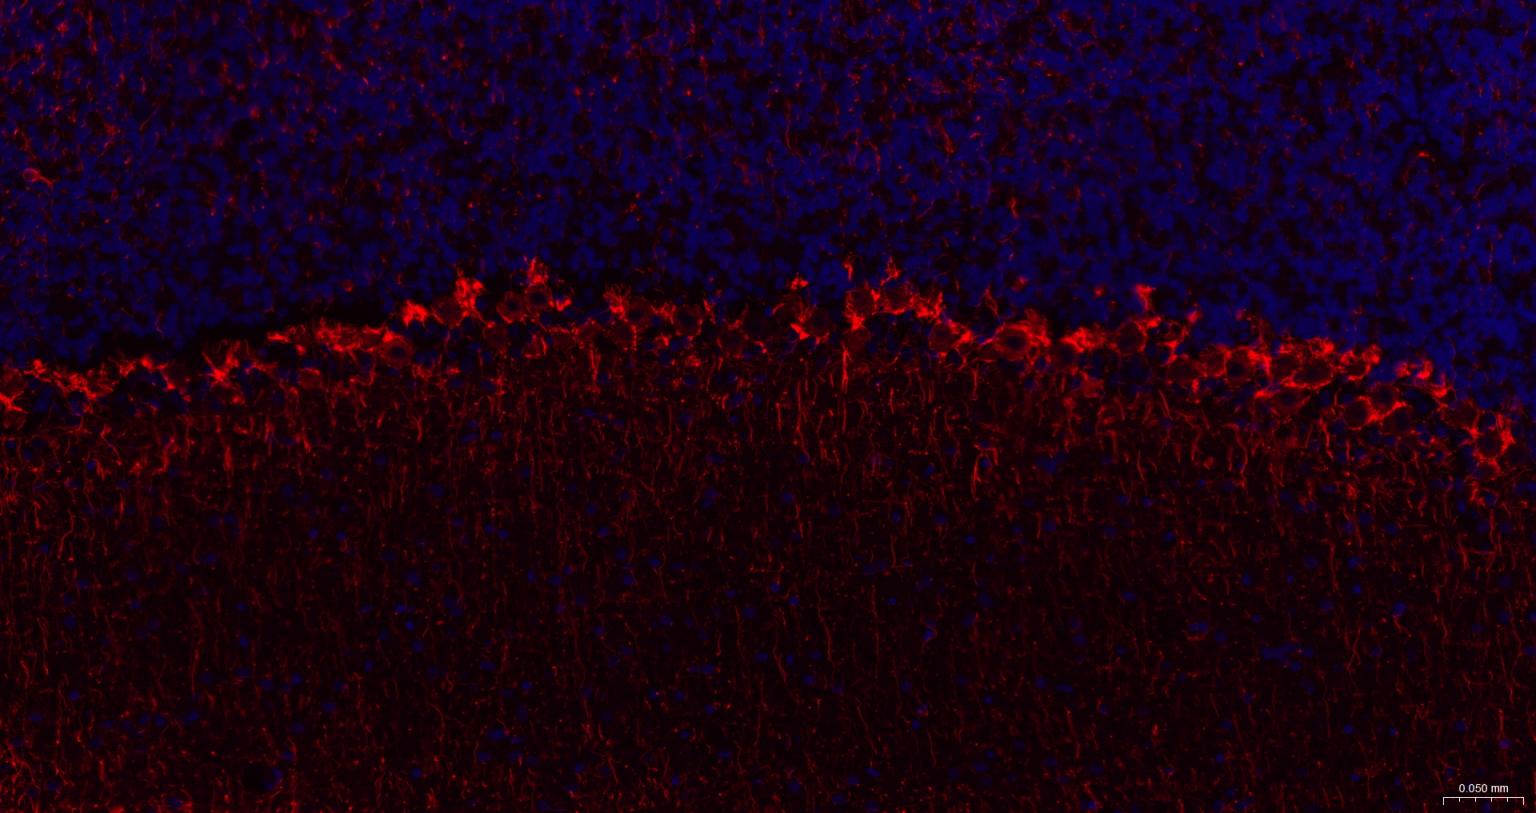

Paraformaldehyde-fixed, paraffin embedded Human Cerebellum; Antigen retrieval by boiling in sodium citrate buffer (pH6.0) for 15 min; The section was incubated with NF-H Monoclonal Antibody, Unconjugated (bsm-60885R) at 1:200 overnight at 4°C. Followed by conjugated Goat Anti-Rabbit IgG antibody (Red, bs-0295G-BF594), DAPI (blue, C02-04002) was used to stain the cell nuclei.

Paraformaldehyde-fixed, paraffin embedded Mouse Cerebellum; Antigen retrieval by boiling in sodium citrate buffer (pH6.0) for 15 min; The section was incubated with NF-H Monoclonal Antibody, Unconjugated (bsm-60885R) at 1:200 overnight at 4°C. Followed by conjugated Goat Anti-Rabbit IgG antibody (Red, bs-0295G-BF594), DAPI (blue, C02-04002) was used to stain the cell nuclei.

Paraformaldehyde-fixed, paraffin embedded Rat Cerebellum; Antigen retrieval by boiling in sodium citrate buffer (pH6.0) for 15 min; The section was incubated with NF-H Monoclonal Antibody, Unconjugated (bsm-60885R) at 1:200 overnight at 4°C. Followed by conjugated Goat Anti-Rabbit IgG antibody (Red, bs-0295G-BF594), DAPI (blue, C02-04002) was used to stain the cell nuclei.